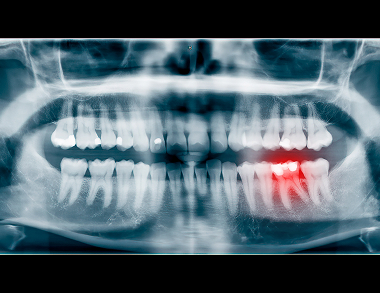

What Dental X-Rays Can Detect

Hidden Decay

Cavities developing between teeth or under existing fillings.

Impacted Teeth

Teeth that are trapped beneath the gums, such as wisdom teeth.

Abscesses & Cysts

Infections at the tooth’s root or other abnormalities within the jawbone.